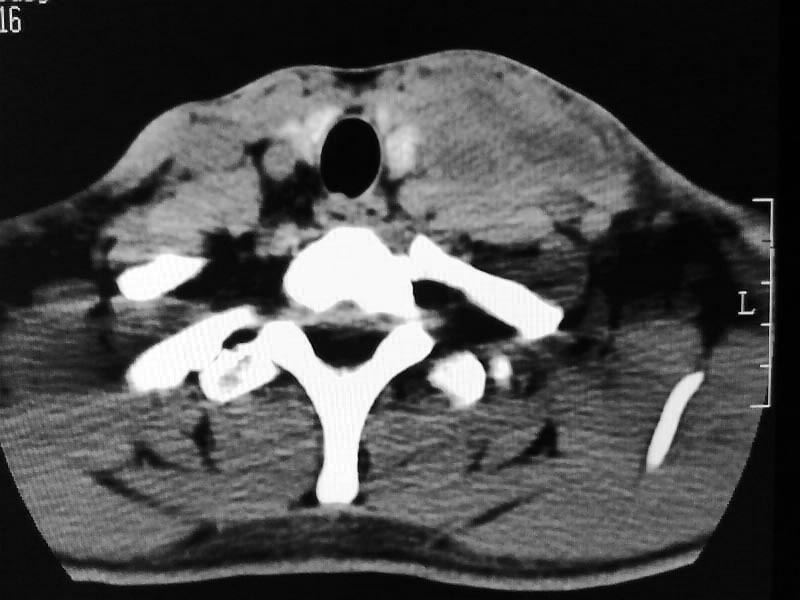

以下是引用余辉在2009-5-3 11:36:00的发言:[br]左侧胸锁乳突肌下方不规则肿物影,边界不清,内部密度不均,左侧颈外侧区脂肪增多,多发淋巴结肿大,考虑淋巴或神经来源肿瘤可能性大,不除外淋巴结炎,肌源性肿瘤及增生性肌炎等,活检